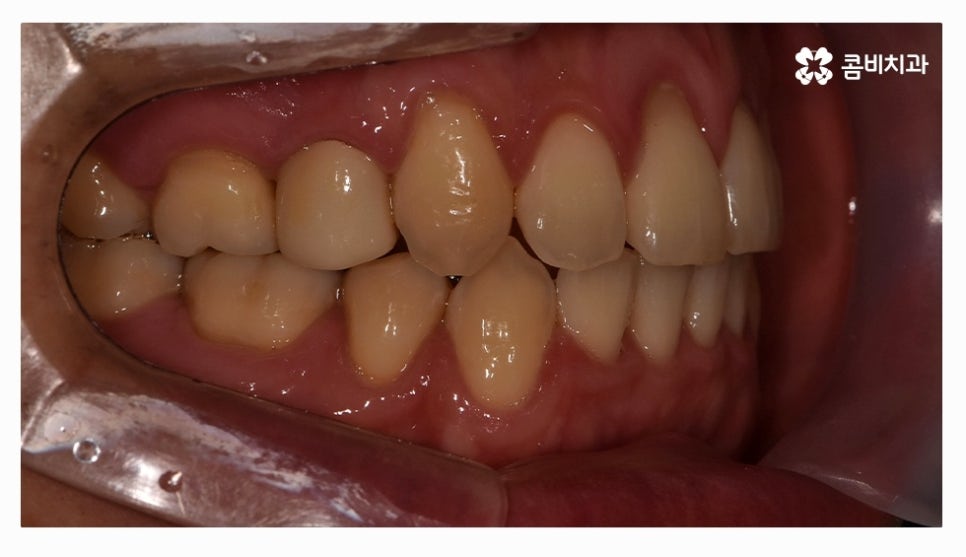

오늘 소개드릴 환자분은 윗니와 아랫니가 제대로 맞물리지 않는

부정교합 사례이며 클리피씨교정을 통해서 치료가 진행된 사례라고 할 수 있어요.

부정교합은 심미적인 부분 외에도 기능적인 부분에 있어서

불편함을 느낄 수밖에 없고 청결관리가 어려워서 나이가 들수록

각종 구강질환이 발생할 확률이 높아질 수 있어요.